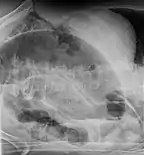

Volvulus with gangrene of the sigmoid

Sigmoid

Treatment for sigmoid volvulus may include sigmoidoscopy. If the mucosa of the sigmoid looks normal and pink, a rectal tube for decompression may be placed, and any fluid, electrolyte, cardiac, kidney or pulmonary abnormalities should be corrected. The affected person should then be taken to the operating room for surgical repair. If surgery is not performed, there is a high rate of recurrence.[10]